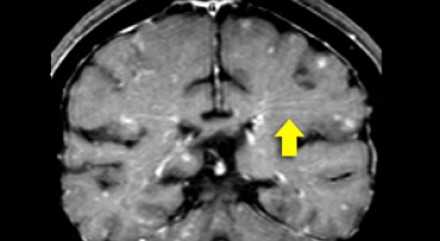

На магнитно-резонансных томограммах продемонстрирована нормальная возрастная картина: расширение борозд, перивентрикулярные «шапочки» (желтая стрелка), «полосы» и точечные очажки в глубоком белом веществе.